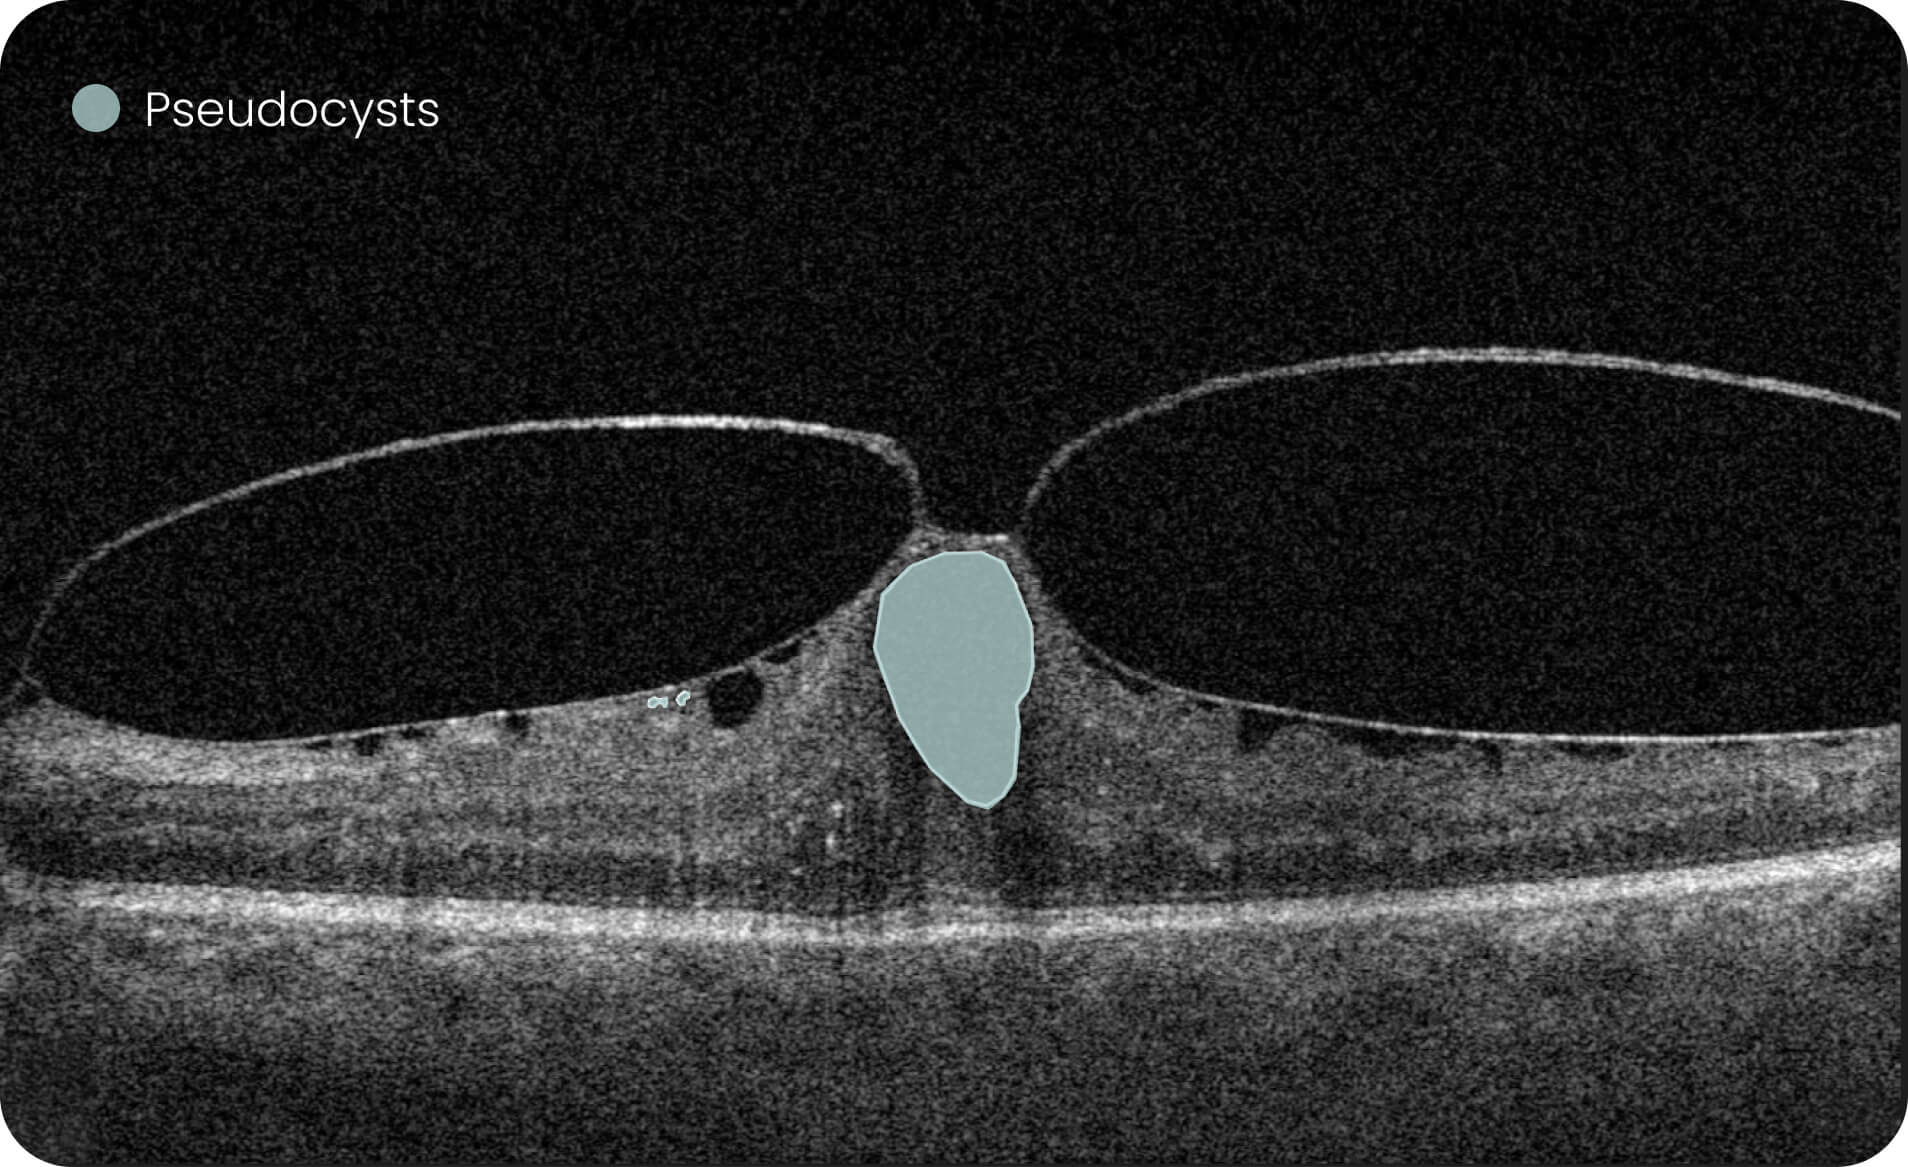

The AI wet age-related macular degeneration in USA platform supports visualization and quantitative, image-derived characterization of OCT imaging features commonly associated with Wet AMD, presented with spatial context on ETDRS-style grids and B-scan views.

Altris AI Models  Research Use Only (RUO). Not for use in diagnostic procedures. These tools enable quantitative, algorithmic exploration of OCT data for research and analytical purposes, including the study of over 40 retinal biomarkers and more than 30 retinal conditions, such as Wet AMD.

• Annotate and explore OCT images for research purposes.

• Quantitative measurements of retinal biomarkers, fluid volume, and drusen count for investigational/analytical purposes only.

Investigation of 40+ retinal biomarkers and 30+ retinal conditions, such as Wet AMD